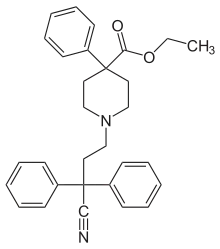

Pirinitramides

Structures

| Pirinitramides | ||||

|---|---|---|---|---|

|

| |||